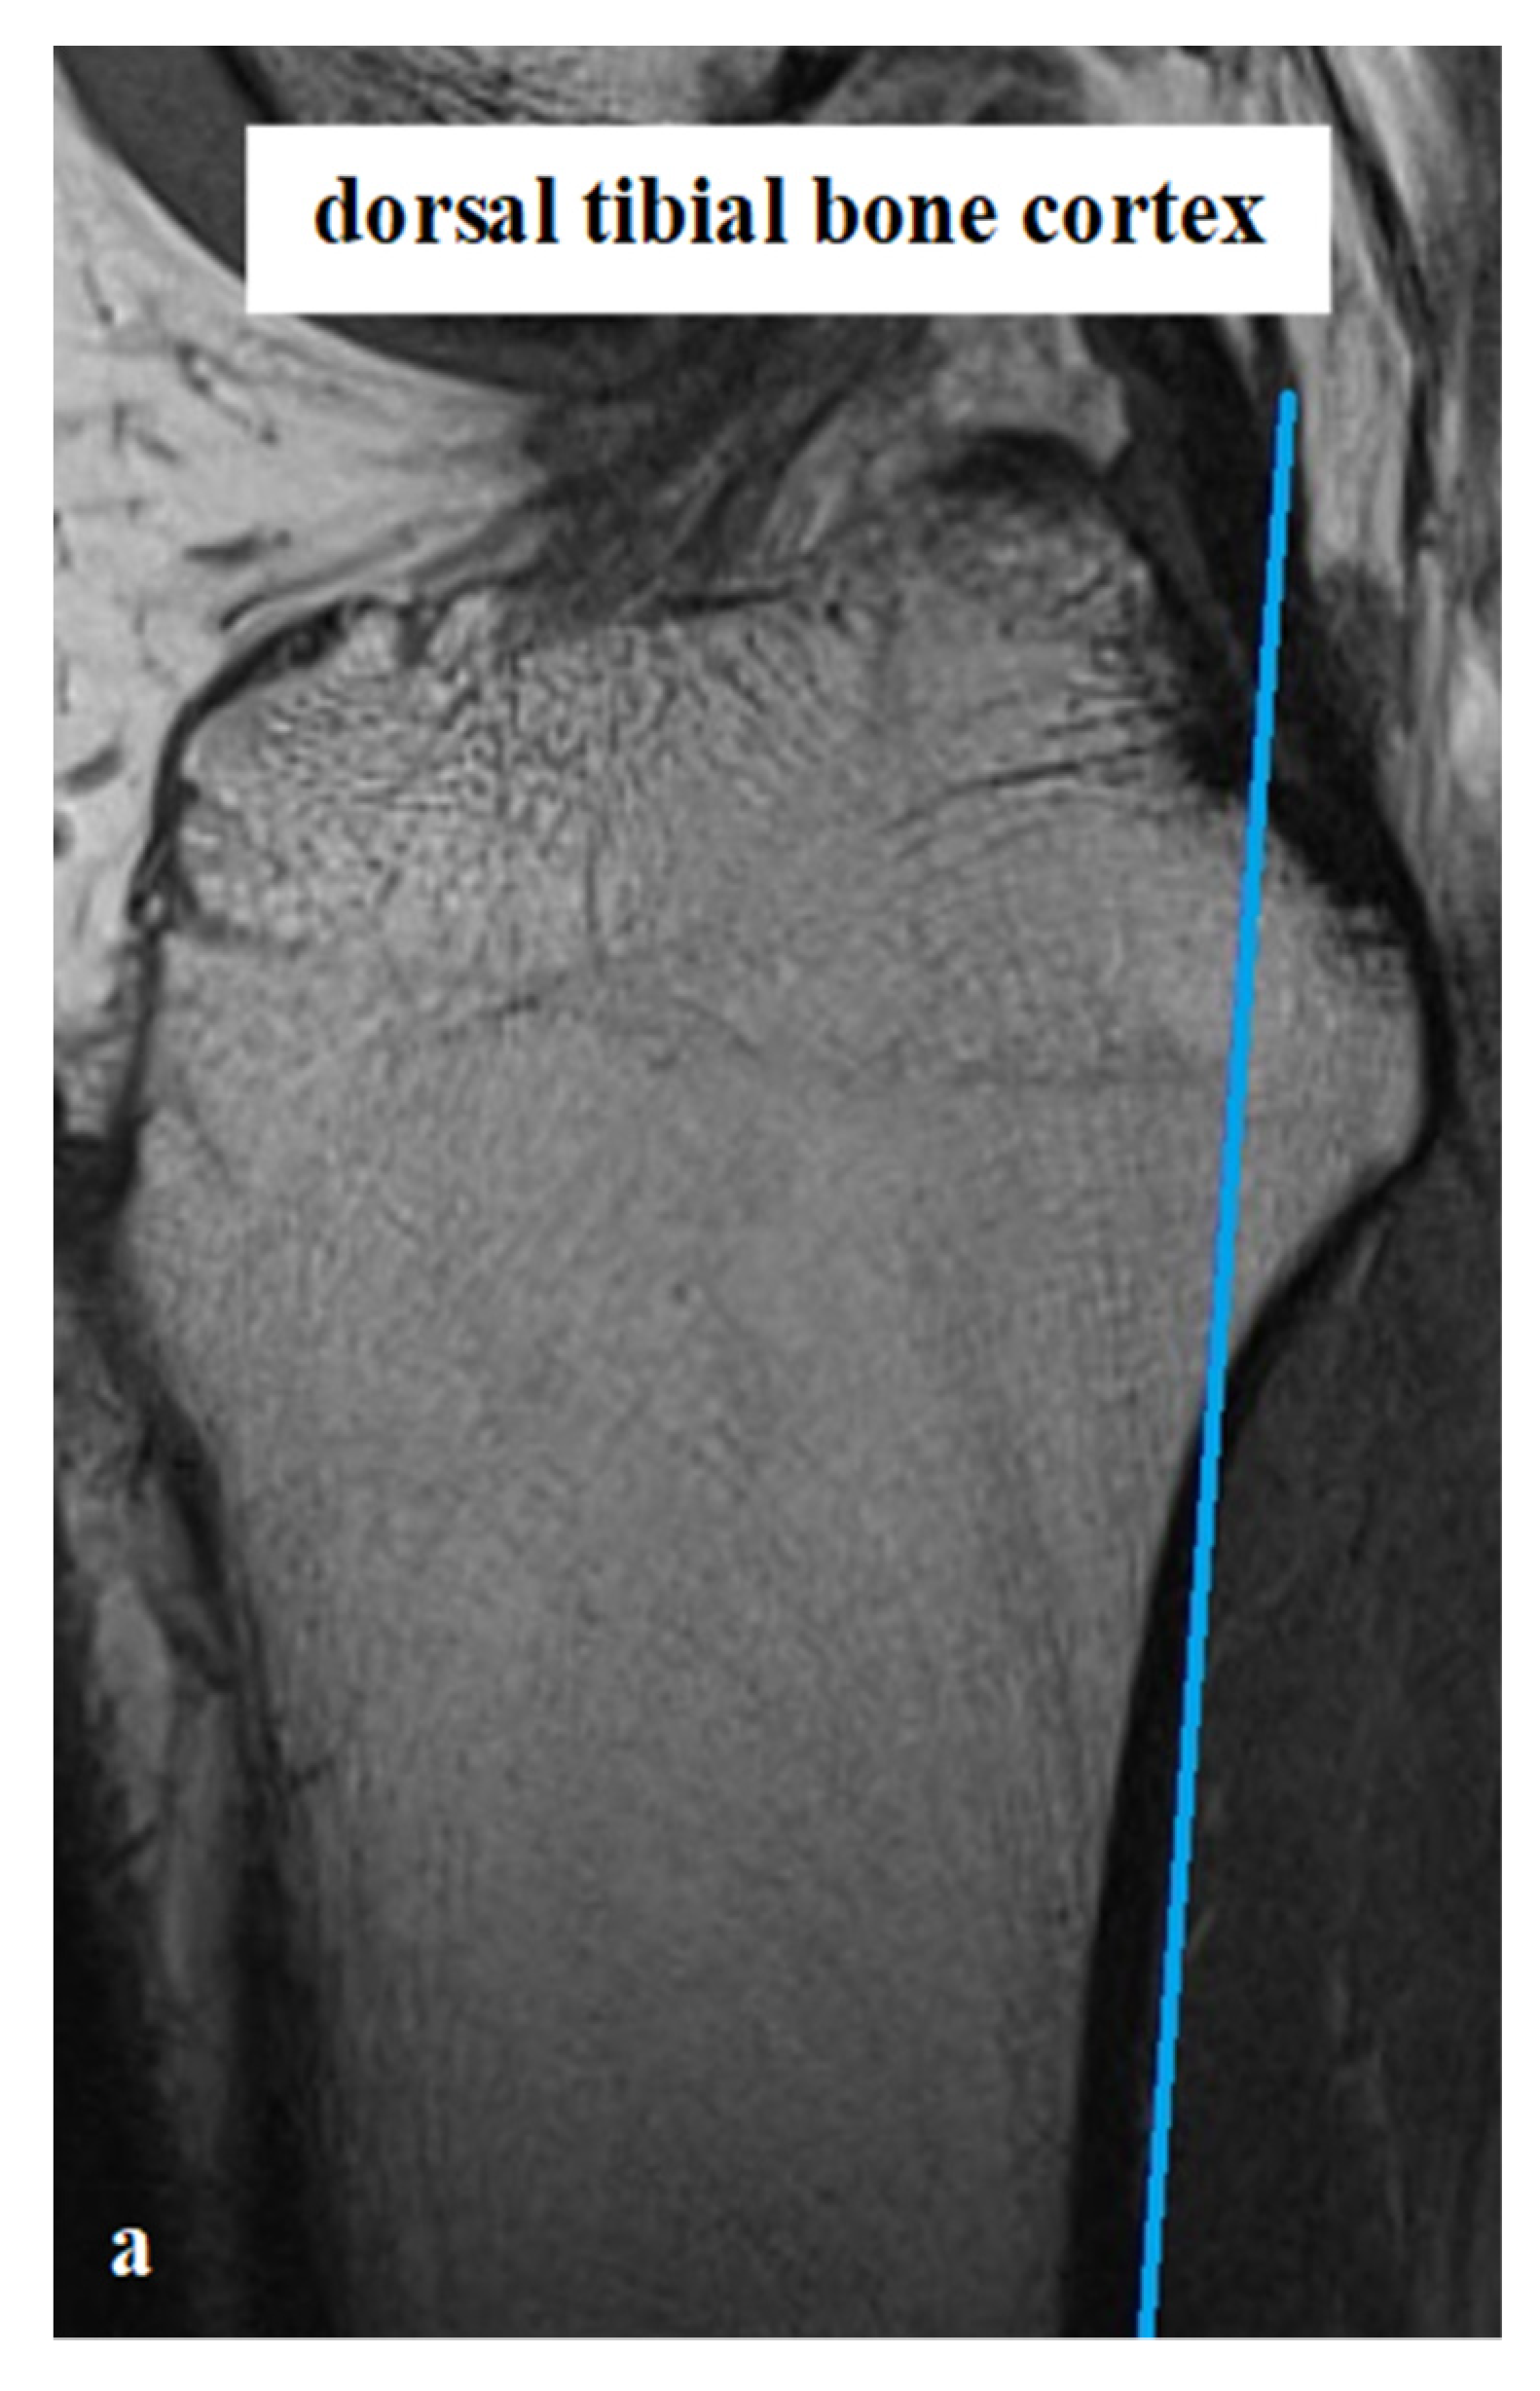

All measurements were taken via the PACS system (Picture Archiving and Communication System). Software from GE Healthcare called CentricityTM Universal Viewer was used (RA1000, edition 2019, Buckinghamshire, Great Britain). The osteoarthritis score of each knee joint was classified according to Kellgren/Lawrence (KL), in order to group patients as KJH or KJD. The TS was measured on the medial and lateral knee-joint surface according to Karimi et al. (TSKmed and TSKlat) [37] and Hudek et al. (TSHmed and TSHlat) [38]. As a reference for determining the inclination of the tibial plateau, Karimi et al. described the dorsal tibial bone cortex and Hudek et al. the tibial-shaft axis. Figure 1 and Figure 2 show the principle of the measurement methodology.

Figure 2.

Exemplary depiction of the measurements of the tibial slope according to Hudek et al. [38] for medial (TSHmed, (b)) and lateral (TSHlat, (c)) knee-joint surface: The measurements of TSH were performed in sagittal view of the knee joint in MRIs. To determine the right position of tibial-shaft axis for each TSHmed and TSHlat, a reference line was set in the best available image. To detect the tibial-shaft axis as accurate as possible, two virtual circle stencils were used (a). The reference structures were the posterior cruciate ligament (PCL) and the intercondyloid eminence (IE). Based on this reference line, the inclination angle of the tibial plateau was determined in the medial (TSHmed, (b)) and lateral (TSHlat, (c)) joint sections.